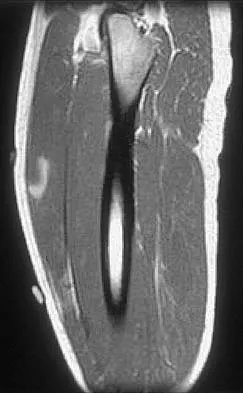

Figure 42 shows the sagittal T2-weighted MRI scan of a patient's right knee. These findings are most commonly seen with a complete tear of the

The MRI scan reveals disruption of the lateral capsule and ligaments with fluid in the soft tissues laterally. Additionally, there is a large bone bruise on the medial femoral condyle. This combination indicates injury to the posterolateral complex. These injuries often have coexisting anterior and/or posterior cruciate ligament injuries. Failure to recognize the posterolateral corner injury can lead to failure of anterior or posterior cruciate ligament reconstructions. LaPrade RF, Gilbert TJ, Bollom TS, et al: The magnetic resonance imaging appearance of individual structures of the posterolateral knee: A prospective study of normal knees and knees with surgically verified grade III injuries. Am J Sports Med 2000;28:191-199.